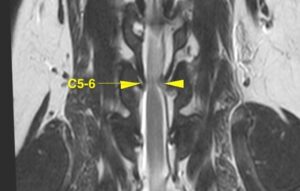

![[MR画像 矢状断像 T2強調画像]](https://saitovet.com/wp-content/uploads/2025/11/2-1-300x195.jpg)

第5および第6頚椎*の間における脊髄が上下から圧迫されている所見があり、明らかな椎間板の突出は認められない。

*首の神経(脊髄)を囲っている骨